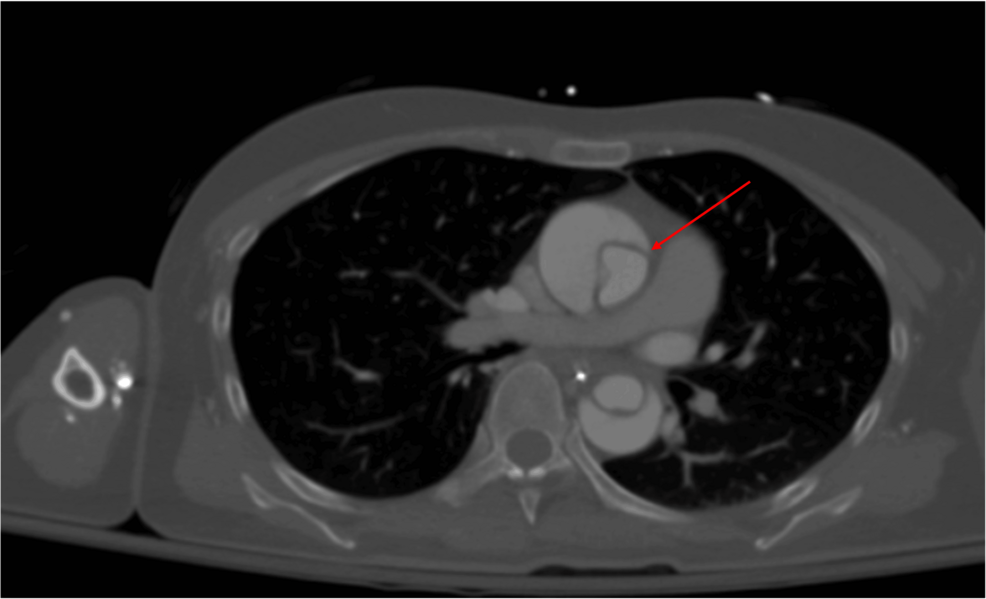

A 56-year-old man is brought to the emergency department 25 minutes after the sudden onset of severe pain in the middle of his chest. He describes the pain as tearing in quality; it radiates to his jaw. He has hypertension. He has smoked one pack of cigarettes daily for the 25 years. Current medications include enalapril. His blood pressure is 154/95 mm Hg in his right arm and 181/105 mm Hg in his left arm. A CT scan of the chest is shown. The structure indicated by the arrow is a derivative of which of the following?